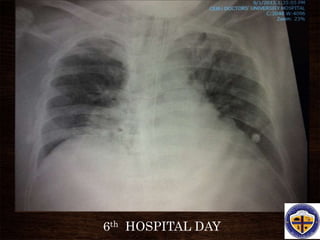

6th HOSPITAL DAY

• #41 A representative anteroposterior chest x-ray in the exudative phase of ARDS shows diffuse interstitial and alveolar infiltrates that can be difficult to distinguish from left ventricular failure.